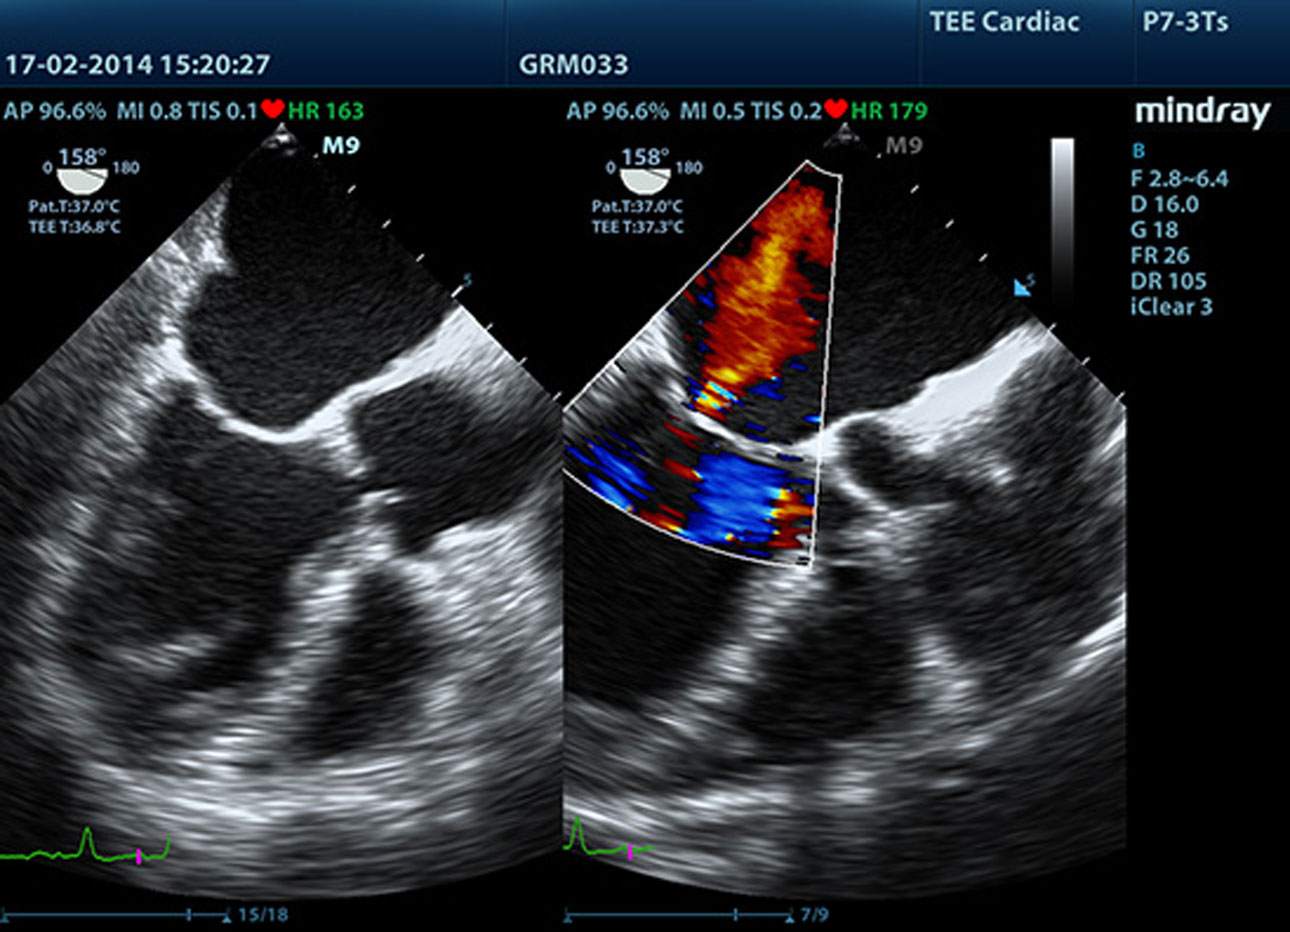

TDI

Tissue Doppler Imaging allows you to quantitatively evaluate local myocardial movement and function, providing complete TDI modes for faster and direct diagnoses.